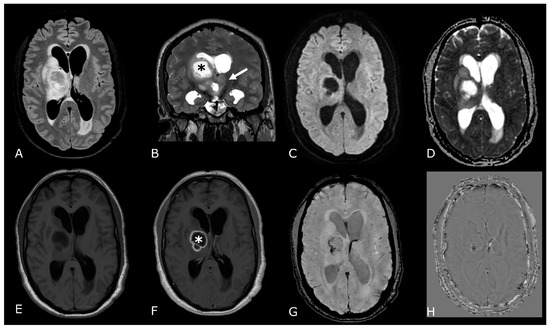

4. Diffusion Weighted and Diffusion Tensor Imaging

4.1. DWI in Brain Tumors: Technical Notes, Clinical Application and Prognosis

4.2. Diffusion Tensor Imaging: Technical Notes and Clinical Application

4.2.1. Tumor Grading and Extension